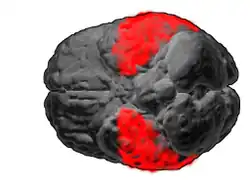

Brodmann area 20, or BA20, is part of the temporal cortex in the human brain. The region encompasses most of the ventral temporal cortex, a region believed to play a part in high-level visual processing and recognition memory.

This area is also known as inferior temporal area 20, and it refers to a subdivision of the cytoarchitecturally defined temporal region of cerebral cortex. In the human it corresponds approximately to the inferior temporal gyrus. Cytoarchitecturally it is bounded medially by the ectorhinal area 36 (H), laterally by the middle temporal area 21, rostrally by the temporopolar area 38 (H) and caudally by the occipitotemporal area 37 (H) (Brodmann-1909).